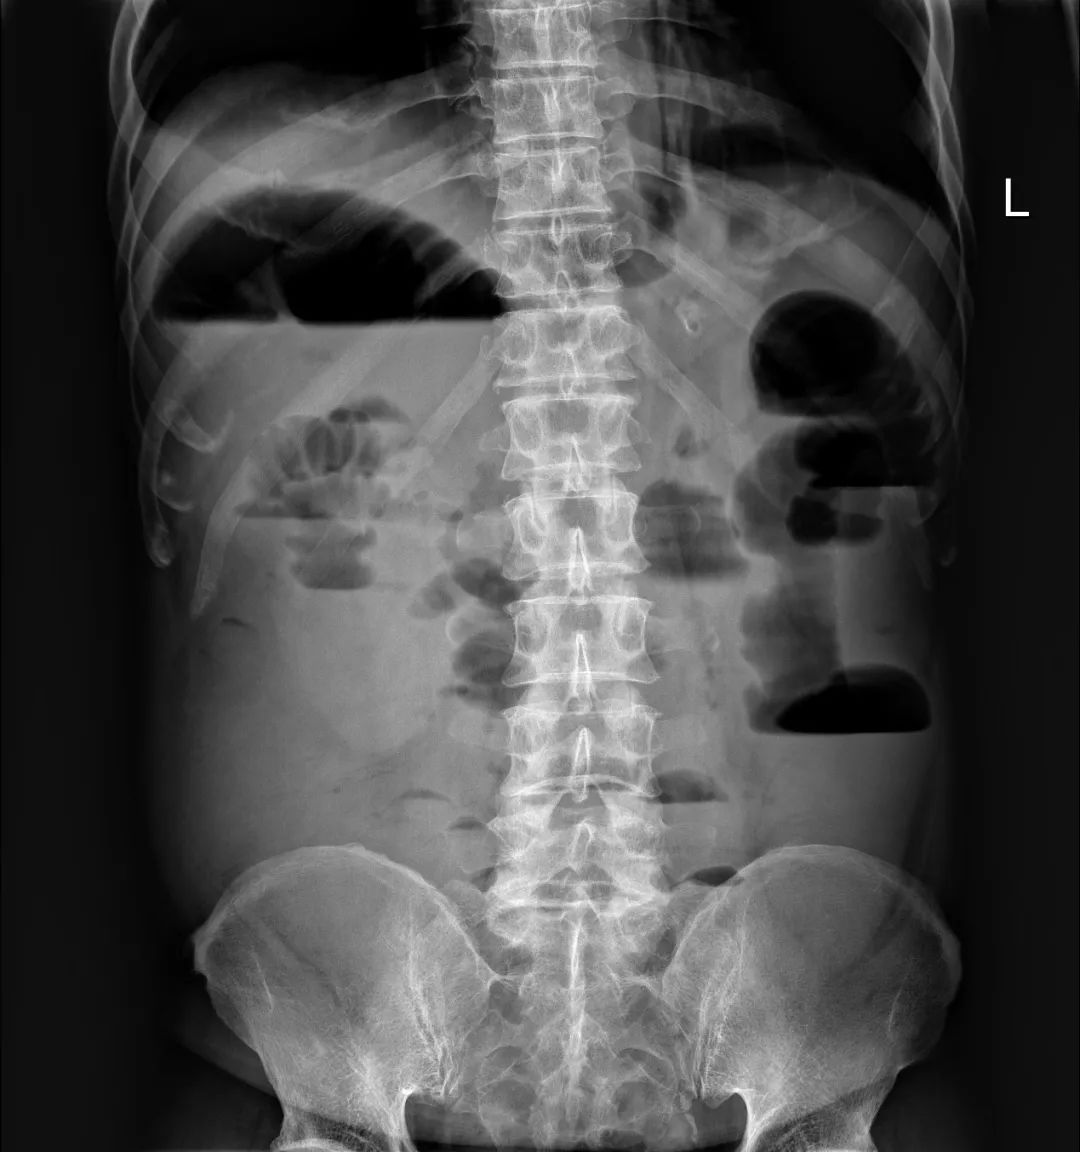

到此为止,患者已经接受了3次大的腹部手术,并接受了放化疗。但是,疾病仍然进展。2018年6月下旬患者出现恶心、呕吐,腹痛、腹胀,不能进食,X线腹部平片及腹部CT检查提示肠梗阻合并感染(见图1、图2),给予抗炎对症治疗效果差。结肠镜检查见横结肠占位伴梗阻(图3)。患者腹痛腹胀进行性加重,出现高热、血压下降等感染性休克症状。患者已经无法耐受再次开腹手术!

图1 腹部X线平片见扩张的肠管和气液平——典型的肠梗阻